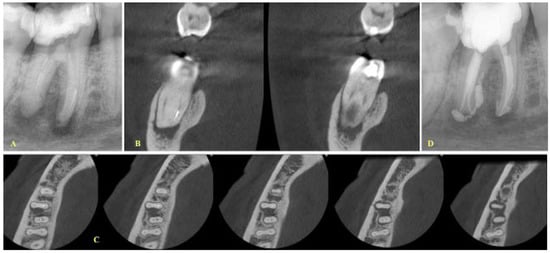

- If the fragment was located at the middle level, the canals were separate and the curvature was not severe as indicated after evaluation of the coronal CBCT images; then, a removal attempt was made, especially in cases where the length of the fragment was short (Figure 2).